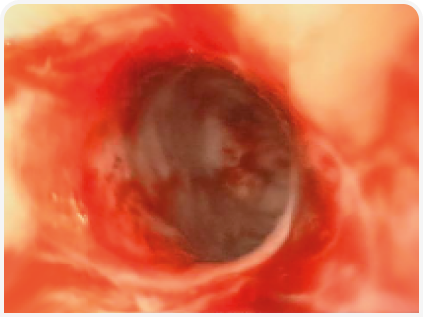

По результатам исследования образцов стенки желудка, полученных методом тонкоигольной аспирационной биопсии под контролем ультразвука, было обнаружено нейтрофильное воспаление. С учетом серьезных подозрений на наличие неоплазии было проведено эндоскопическое исследование желудка. При этом патологических изменений пищевода, дна желудка и большой кривизны обнаружено не было, однако малая кривизна и антральный отдел характеризовались ригидностью и не поддавались расширению при инсуфляции; язвенных поражений не обнаружили. Тяжесть поражений привратника делала невозможным прохождение эндоскопа через пилорус (Рисунок 8).